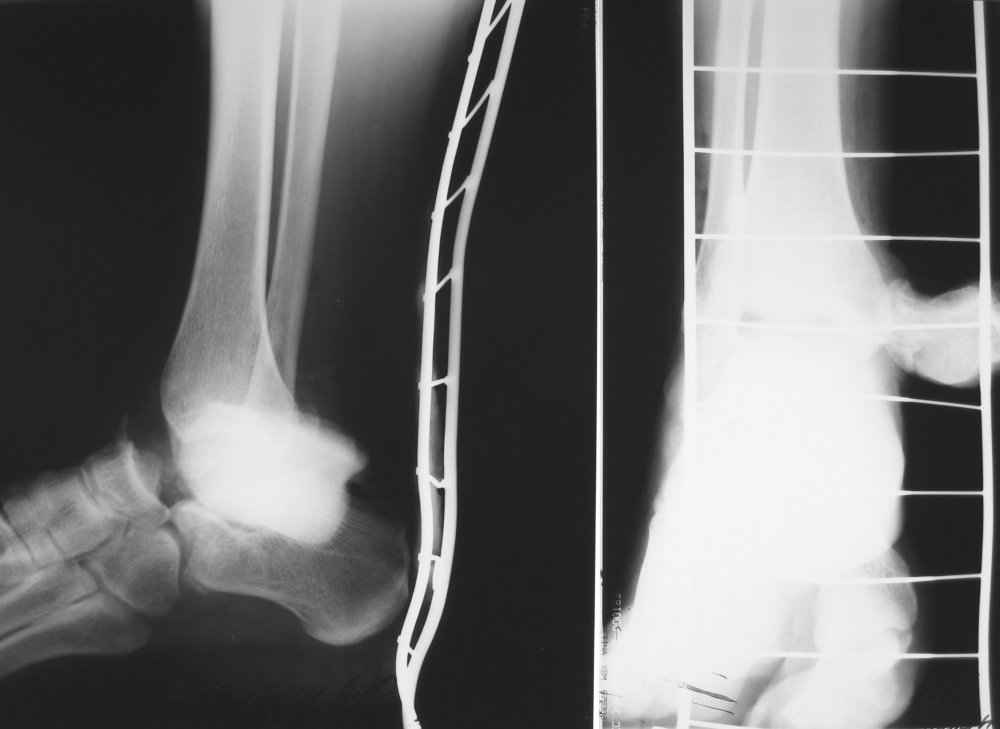

На лечении находится пациент 35 лет. Травма в сентябре 2008 г.- открытый вывих таранной кости

В день травмы ПХО, вправление вывиха, трансартикулярная фиксация. Рана зажила первично. С января нагрузка на конечность. С конца апреля- болевой синдром. На рентгенограммах и КТ признаки ас. некроза таранной кости, артроз подтаранного и голеностопного суставов.

У больного тотальный ас. некрох блока таранной кости, заинтересованы голеностопный и подтараный суставы. Эндопротезирование маловероятно на некротизированную кость. Изолированный подтаранный артродез таран не спасет.При артродезе всю некротизированную кость придется убрать.А далее замещение либо за счет большеберцовой кости, или удлинение на регенерате.